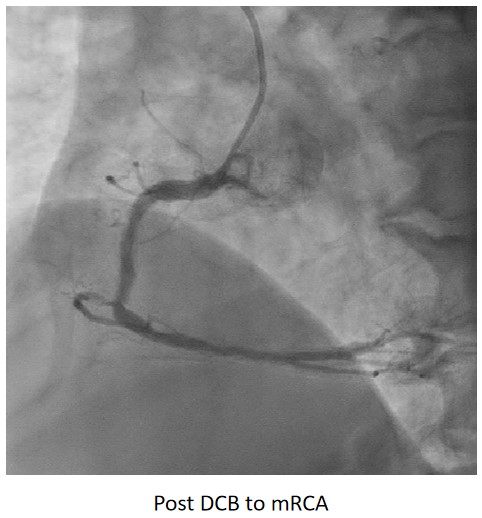

Urgent coronary angiography showed smooth LMCA with severe 3-vessel involvement. There was diffuse LAD lesion with critical stenosis at proximal-to-mid segment. Mid-segment of LCx was 90% stenosed while RCA was heavily calcified with critical stenosis at its mid segment. Our strategy will be complete revascularisation by employing DCB-only strategy.

Complete revascularisation was achieved with 2-staged procedures. Up-front plaque modification with rotational atherectomy/IVL with IVUS was planned but limited by patient¡¯s cost constraint. Vascular access obtained with transradial puncture with 6 Fr sheath. Guiding catheter (GC) Judkins Right 4.0 (Cordis, USA) 6 Fr was used to engage right coronary ostium. Runthrough Floppy (Terumo, Japan) wire was wired down RCA. Pre-dilatation balloons were unable to cross the heavily calcified mRCA lesion. Next, GC was changed to Amplatz Left 1.0 (Cordis, USA) for better support and proceeded for further lesion preparation with cutting balloon Wolverine (Boston Scientific, USA) 3.5 x 10 mm and DCB Prevail (Medtronic, USA) 3.0 x 20 mm was deployed. We scheduled him for staged PCI to the left coronaries in 2 weeks time via transradial approach with 6 Fr sheath. GC XB LAD 3.5 (Cordis, USA) 6 Fr was used to engage left coronary ostium. Runthrough Floppy was wired down LCx. Mid-distal LCx was prepared with Pantera Pro (Biotronik, Germany) 2.5 x 15 mm and DCB Pantera Lux (Biotronik ,Germany) 3.0 x 15 mm was deployed. Finally, we wired down LAD with Runthrough Floppy. Mid-distal LAD lesion was prepared with Pantera Pro 2.5 x 15 mm and DCB Pantera Lux 3.0 x 30 mm was deployed. Proximal LAD lesion, which was calcified, was further prepared with Wolverine 2.5 x 10 mm before DCB Pantera Lux 3.5 x 30 mm was deployed. Final post-PCI results were acceptable, achieving complete revascularisation for him.